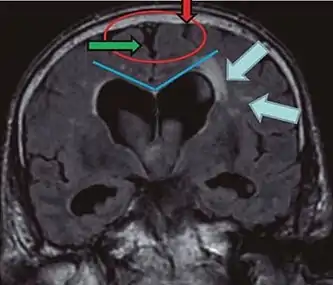

• Imaging from magnetic resonance imaging (MRI) or computed tomography (CT) is needed to demonstrate enlarged ventricles and no macroscopic obstruction to cerebrospinal fluid flow. Imaging should show an enlargement to at least one of the temporal horns of lateral ventricles, and impingement against the falx cerebri resulting in a callosal angle ≤ 90° on the coronal view, showing evidence of altered brain water content, or normal active flow (which is referred to as "flow void") at the cerebral aqueduct and fourth ventricle.

Typical imaging findings in normal pressure hydrocephalus versus brain atrophy.[9]

Normal pressure hydrocephalusBrain atrophy

Preferable projectionCoronal plane at the level of the posterior commissure of the brain.

Modality in this exampleCTMRI

CSF spaces over the convexity near the vertex (red ellipse )Narrowed convexity ("tight convexity") as well as medial cisternsWidened vertex (red arrow) and medial cisterns (green arrow)

Callosal angle (blue V)Acute angleObtuse angle

Most likely cause of leucoaraiosis (periventricular signal alterations, blue arrows ) Transependymal cerebrospinal fluid diapedesis Vascular encephalopathy, in this case suggested by unilateral occurrence